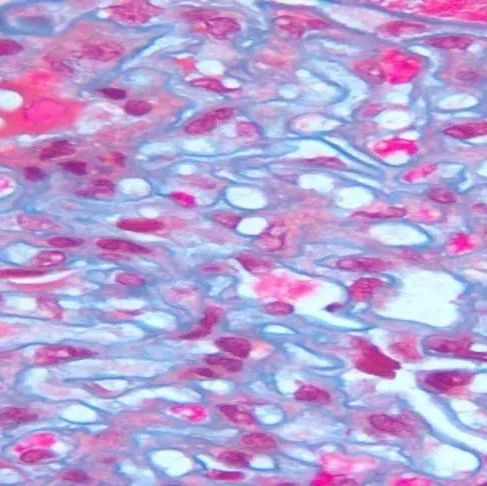

• 显微镜下的“显眼胞”-ALK阳性间变大细胞淋巴瘤